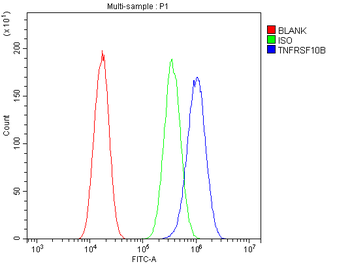

10 μg, 100 μg - Anti-DR5/TNFRSF10B Antibody [orb389514]

FC, IHC, WB

Human, Mouse, Rat

Rabbit

Polyclonal

Unconjugated

10 μg, 100 μg - Anti-Annexin IV/ANXA4 Antibody [orb18546]